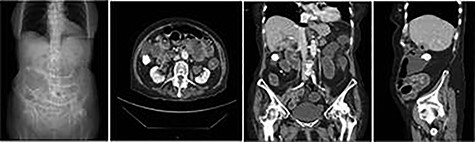

Plain abdominal X-ray demonstrated a calcified lesion on the right as well as distended loops of small bowel (Fig. 1). Abdomino-pelvic contrast CT scan showed an abnormal gallbladder containing pockets of air and a fistulation through the lateral part of D2,with a 22 mm calcified lesion within the ascending colon (Fig. 2a–d). Based on the history, physical examination and CT scan findings, our diagnosis was of resolving gallstone ileus.

a,b,c,d: CT images scout, axial, coronal and sagittal planes, respectively demonstrating gallstone as well as distended loops of small bowel.